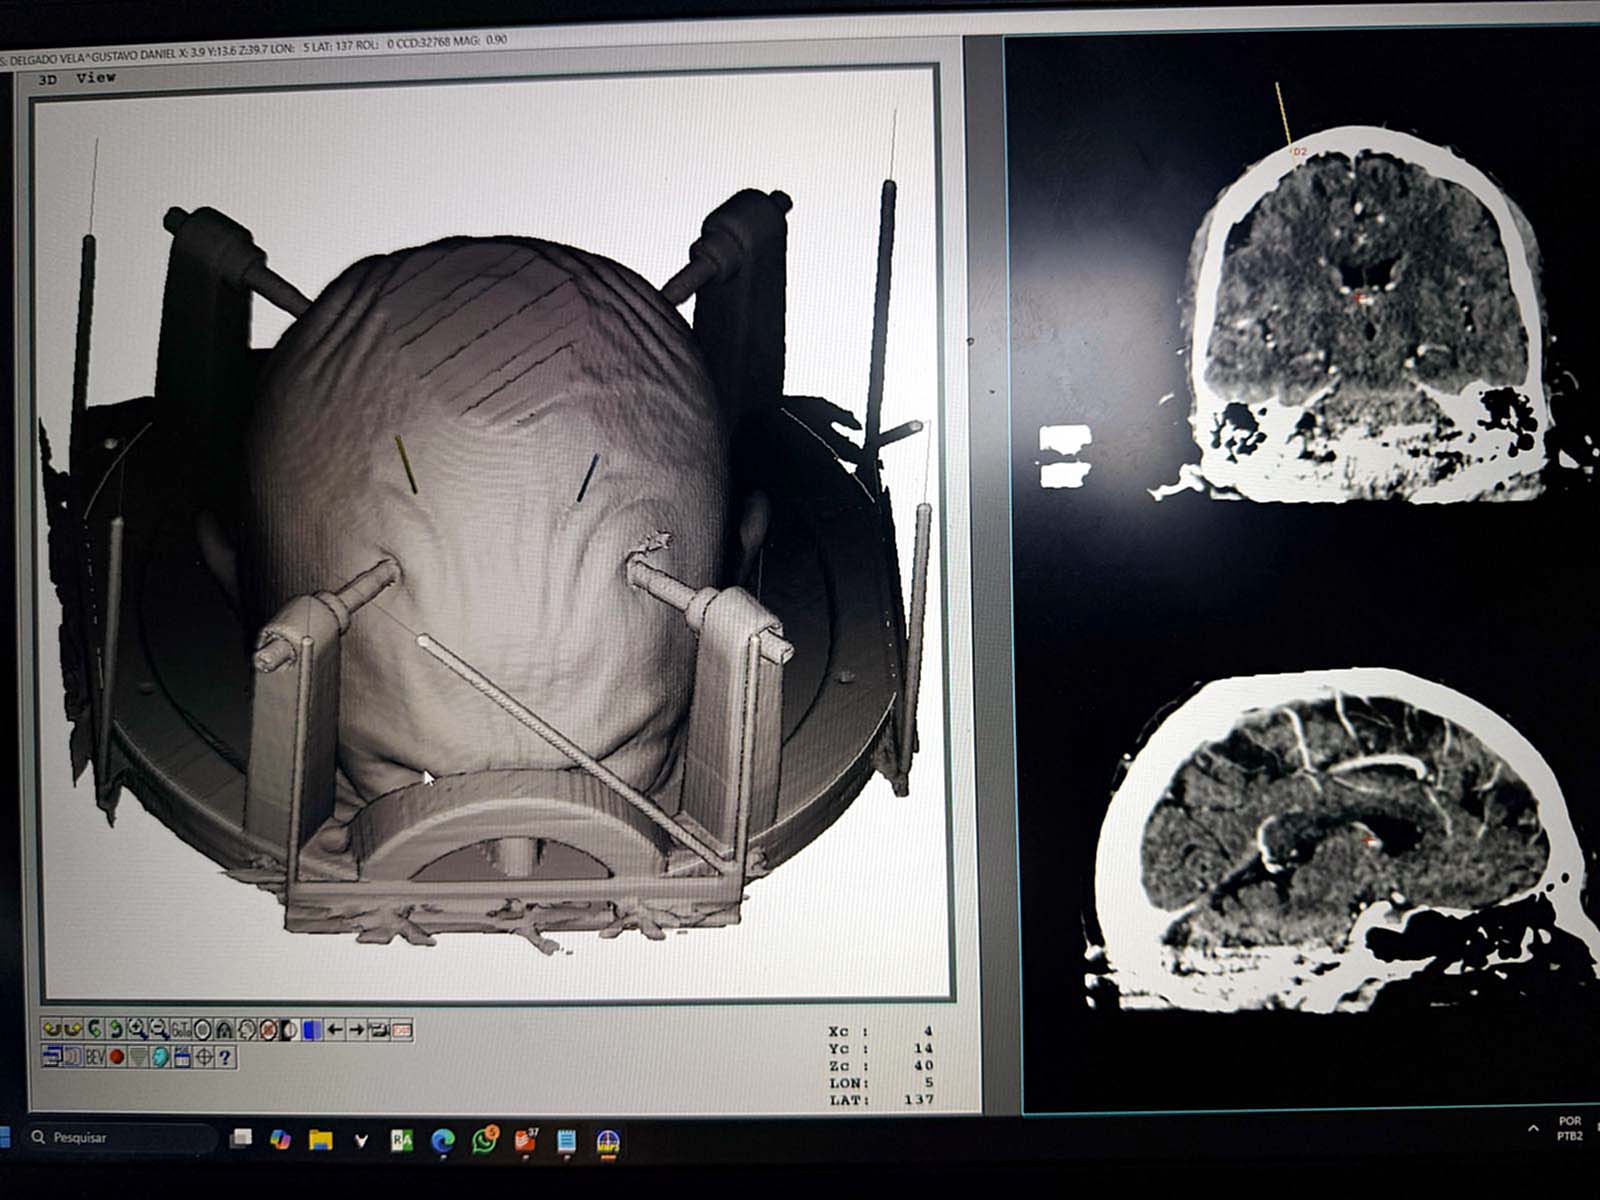

La cirugía consiste en la implantación de un estimulador cerebral profundo, que son electrodos colocados a nivel de los ganglios basales.

1. Primera etapa con el paciente despierto, evaluando la respuesta clínica a la estimulación.

2. Segunda etapa bajo anestesia, donde se instala el generador o “batería” bajo la piel.